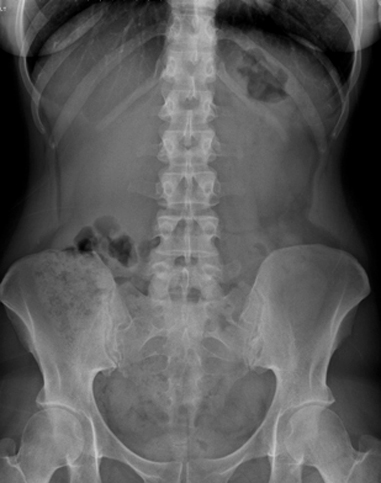

Images radiologique normale du cliche ASP de

face :

-En haut ce sont les deux coupoles

diapragmatique limitant la cavite abdominale

- En bas c'est le pelvis |

- En haut et laterale ce sont des

dernieres cotes |

- Au centre : La region dorsolombaire , le rachis lombaire

et puis l'ombre des organe pleins : L'opacite du foie au

niveau de la region sous diphragmatique droite par

lobe droit et sous diapragmatique gauche par lobe

gauche . L'opacite de la rate est a gauche ,

sous diapragmatique gauche et externe . A inferieure

et pres de la colon vertebrale c'est l'ombre des

deux reins( l'ombre renale ) . L'opacite de deux

muscle de psoas peut en voyait de chaque cote de la

colonne lombaire au debut de D12 , L1 incline a deux

fosses iliaques . L'opacite de la vessie en se

voyait lorsqu'elle est en repletition ou en

semi-repletition |

- Le tube digestif : Il est visible

lorsqu'il contient de l'air , |

-L'estomac est toujour

visible et la presence d'air gastrique est normale .

Il situe sur le quadrant superieure gauche de

l'abdomen , la poche gastrique est directement sous

diapragmatique gauche et oblique a inferieure et

attache au transverse colon par ligament gastro-colique

. Image le plus souvent en voyait est image hydro-aerique

de la poche gastrique et sa diametre est variable |

- Le grele du jeune enfant contient toujour d'air mais

le grele de aldulte ne contient pas ou tres peu . .Situe

au centre de l'abdomen et en circle par des plies

muqueuses et il peut efface en distendue . Sa

diametre peut atteint 30mm |

- Colon contient toujour d'air et le plus

souvent est le ceacum , angle colique droit , angle

colique gauche . Et dans image de gaz du colon on

peut voyait encore image des selles de sa

contenant . |

- Lateralement a gauche et a droite est

image claire de la petite lame de graisse de la

paroi de l'abdomen , . en dedans est le peritoine .

Entre le peritoine et le colon descenant , ascendant

est gouttiere parieto-colique |

| 1 Coupole diaphragmatique Dt |

| 2 Colonne vertebrale |

| 3 Gas dans gros tuberosite de

estomac |

| 4 Gaz situe dans l'angle colique

gauche |

| 5 Gaz du colon transverse |

| 6 Gaz du colon Sigmoide |

| 7 Saccrum |

| 8 Crete iliaque |

| 9 Tete femorale |

| 10 Gaz situe dans angle colique

droit |

| 11 Bord de silhouette de psoas |

| 12 Sombre du foie et rein droit |

| 13 onzieme cote |

| 14 Ligne graisseuse de la paroi de

abdomen |